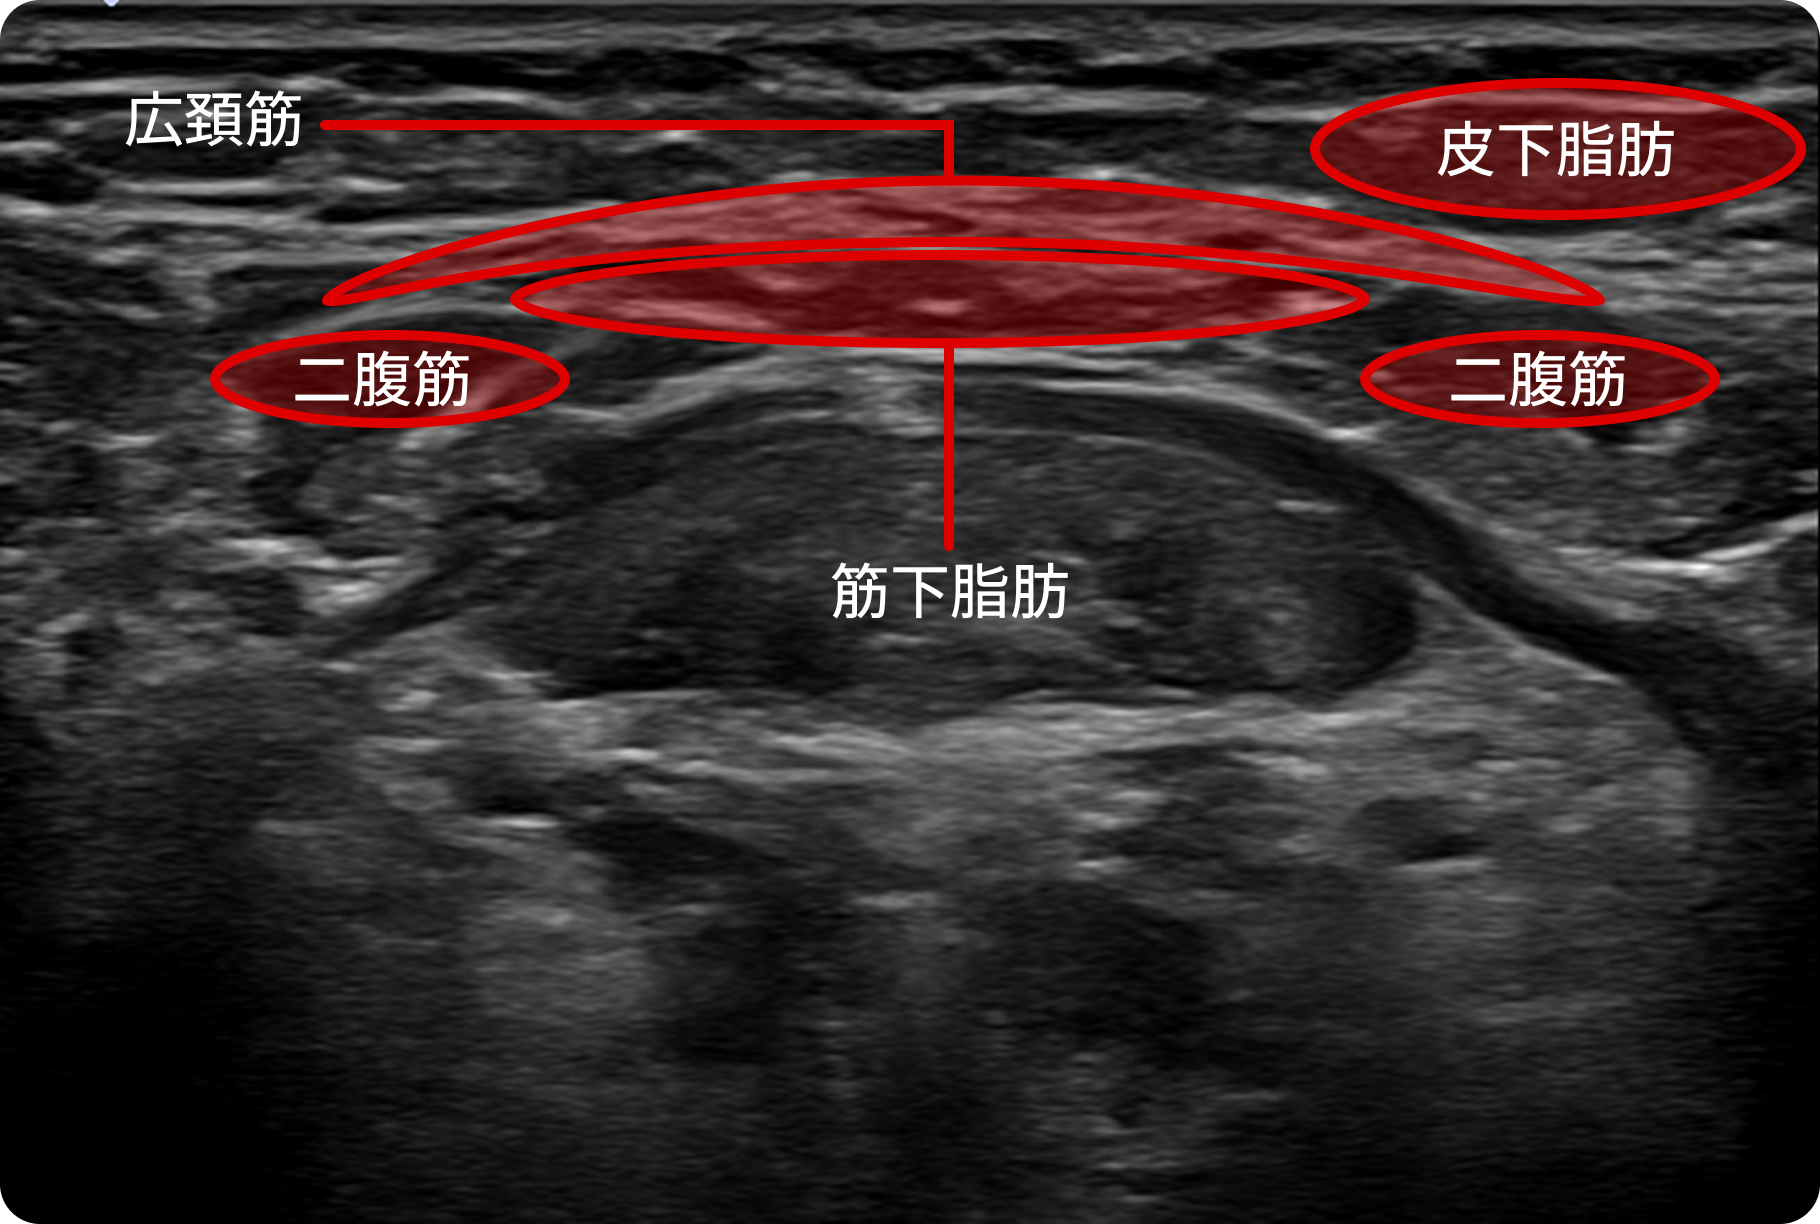

安全に、必要な脂肪だけを選択的に除去

超精密検査 — より安全で完璧な手術への第一歩